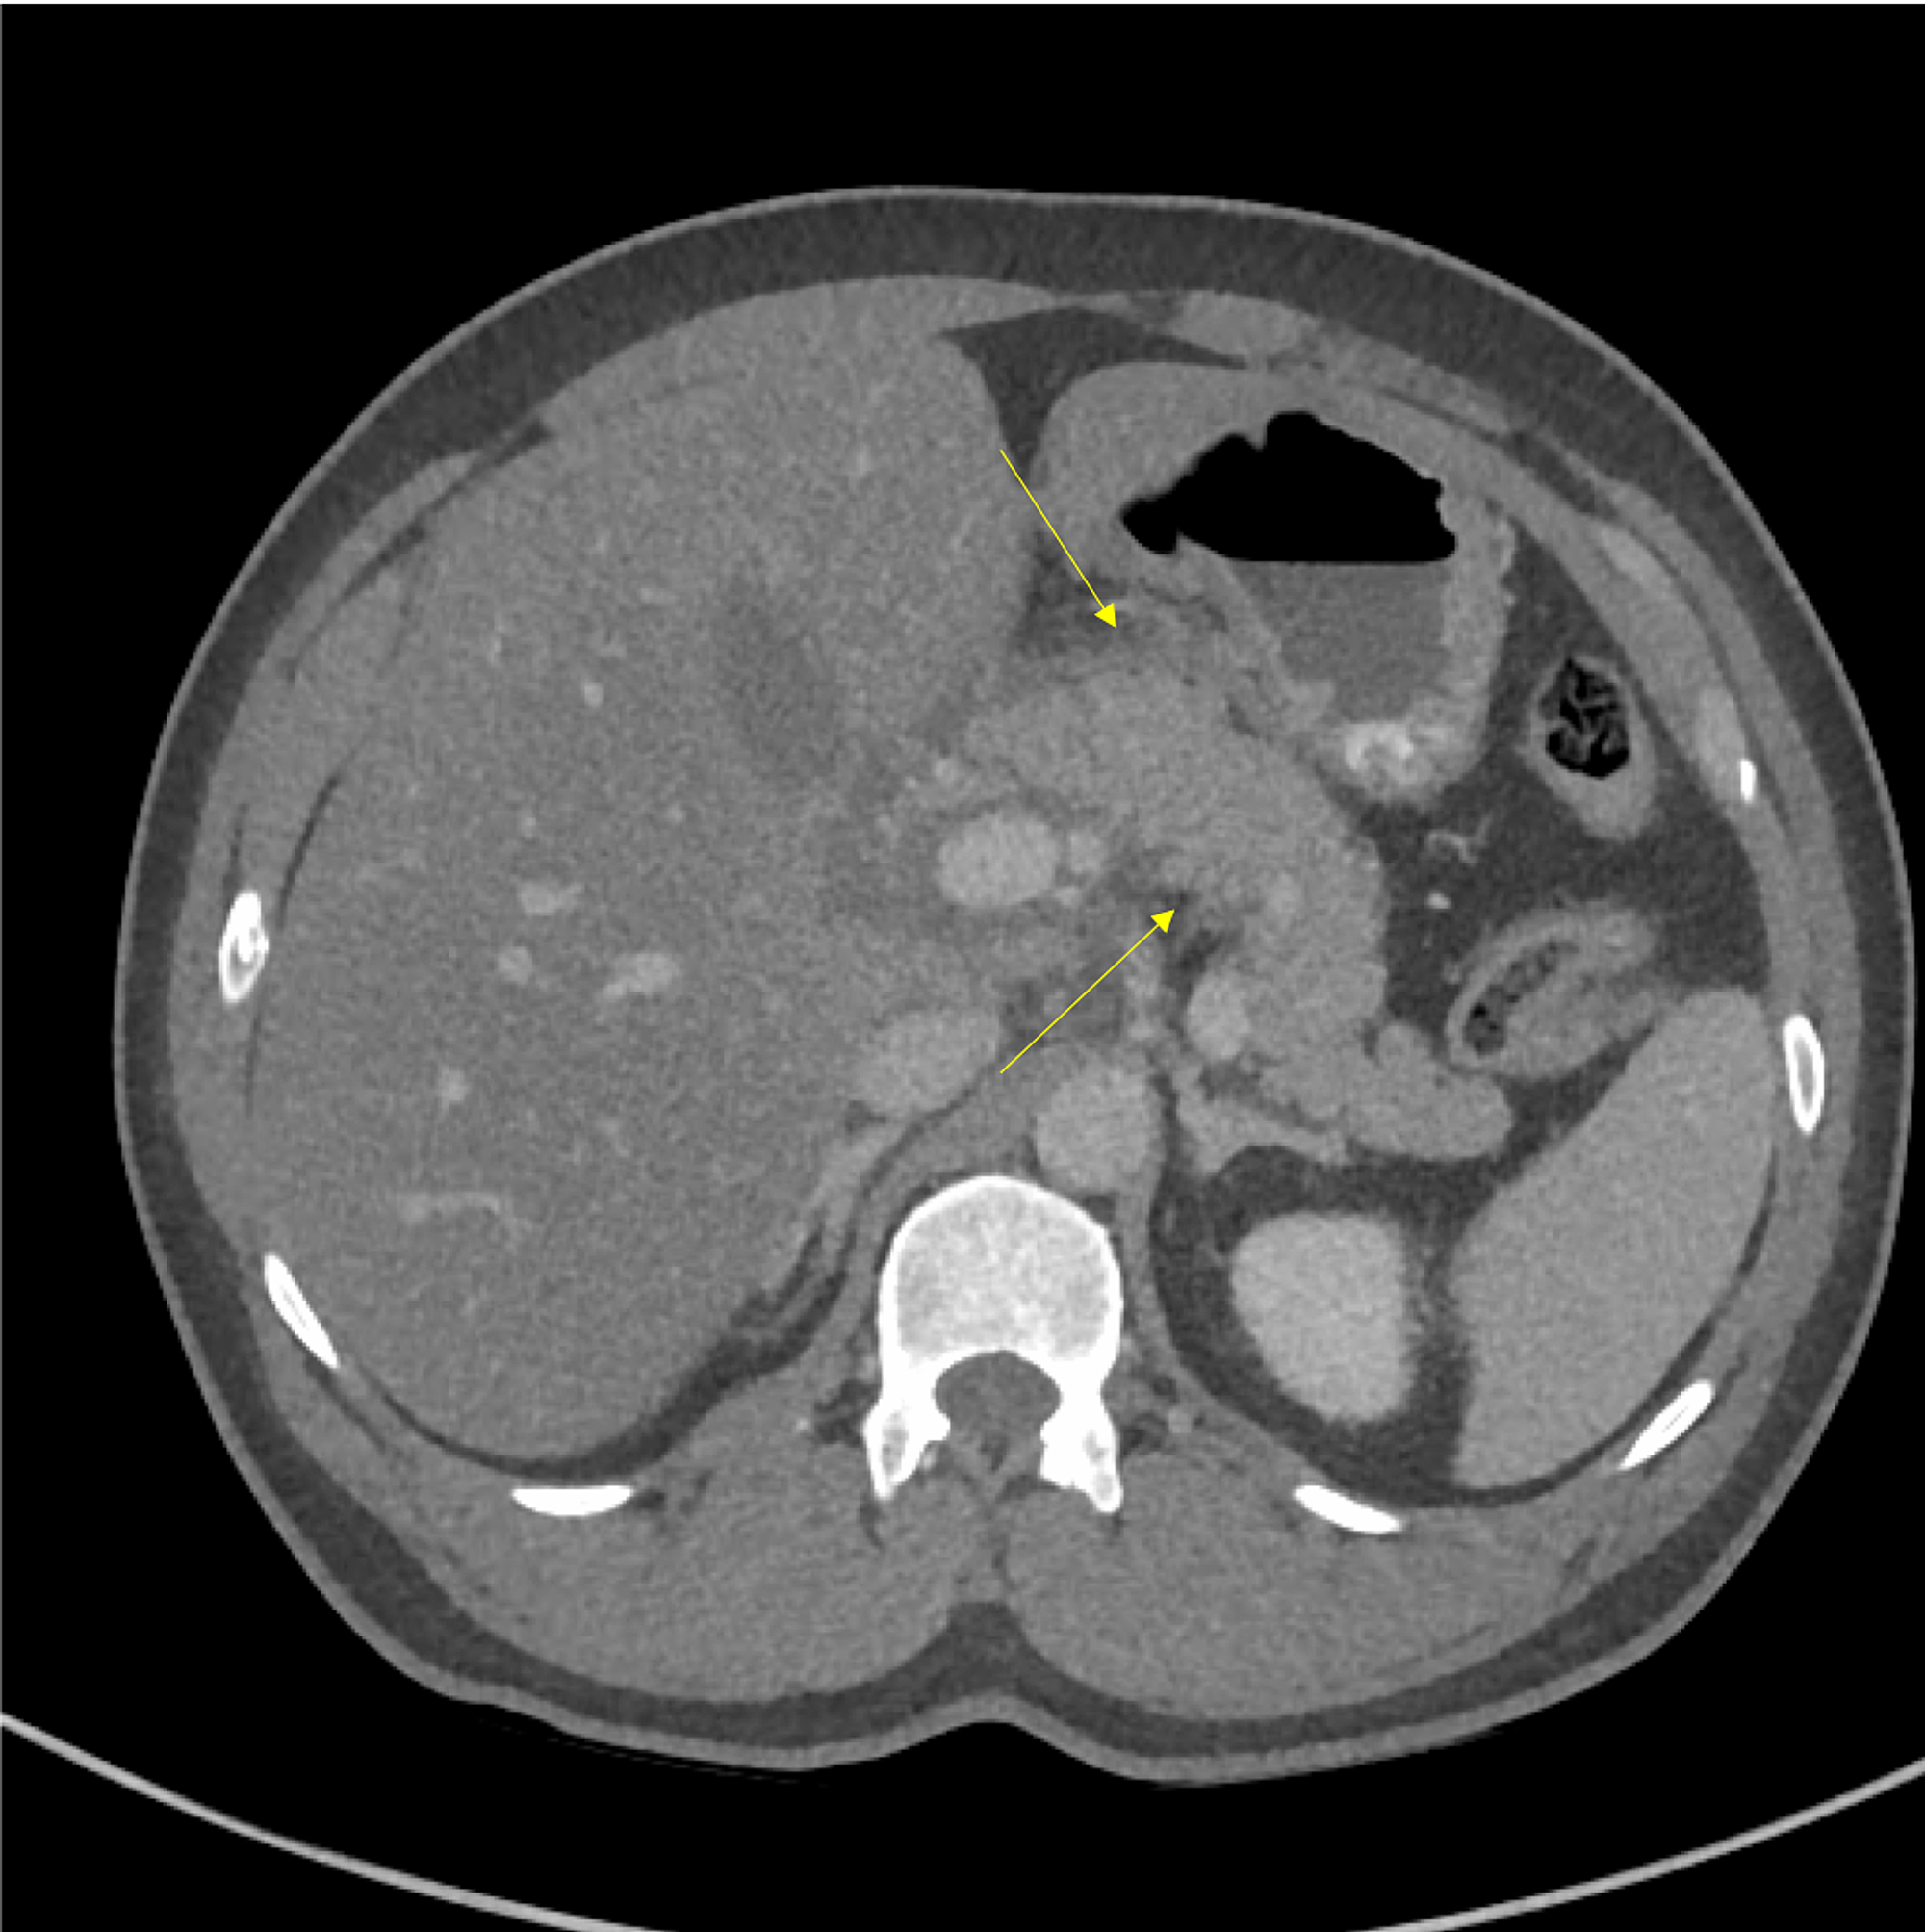

After five days, feeding through a Dobhoff tube was initiated. Despite the improvements in abdominal tenderness and triglyceride levels, one episode of fever (38.5 °C) was observed. A repeat CT scan of the abdomen with contrast revealed partial PVT (Figure 3), and enoxaparin was initiated.